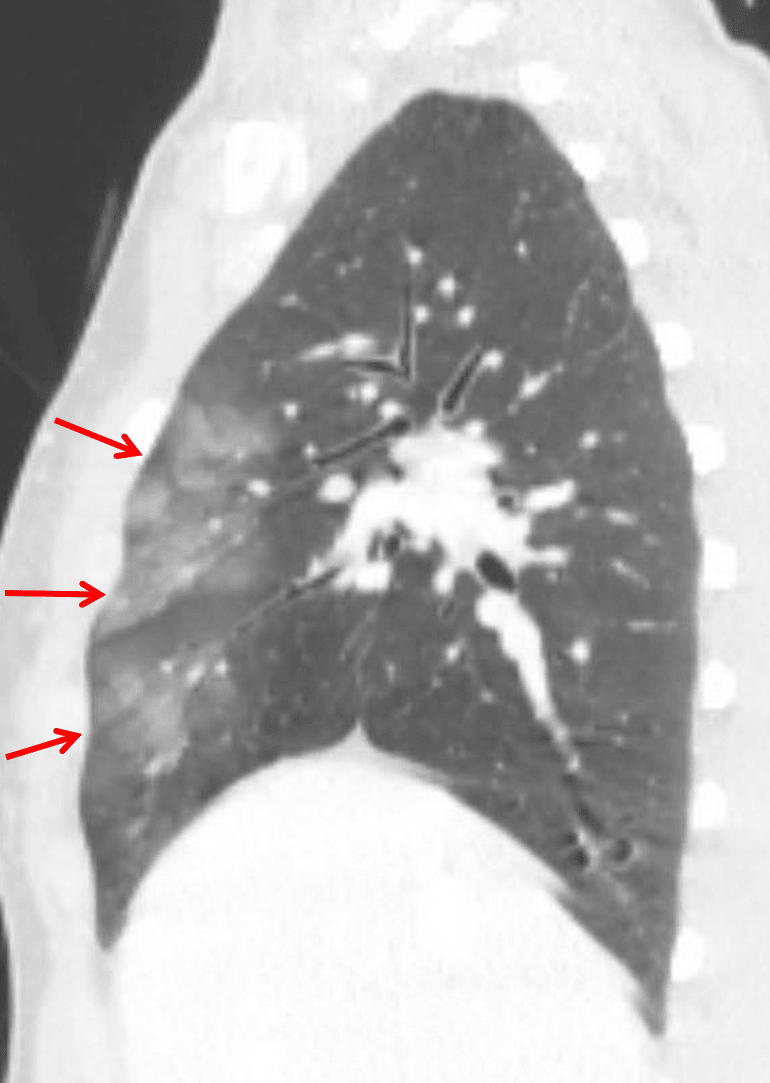

- Mild peripheral groundglass opacities in the anterior aspects of the right upper and middle lobes and to a lesser extent in the lingula

Pulmonary contusion

Pulmonary contusion in the anterior aspects of the right upper and middle lobes and to a lesser extent in the lingula.

- Pulmonary contusion is often located in a non-dependent area of the lung and correlates with the site(s) of blunt chest trauma

- Pulmonary contusion will typically resolve within a few days with supportive management, so if you see groundglass opacities persisting a week or more after trauma or appearing more than 24 hours after trauma, there is likely something else going on

- If you see bilateral dependent groundglass opacities, this is more likely to represent subsegmental atelectasis or aspiration

- Make sure to look for associated pulmonary laceration or pneumatocele

Pulmonary contusion: groundglass opacities in the anterior aspects of the right upper and middle lobes (red arrows).